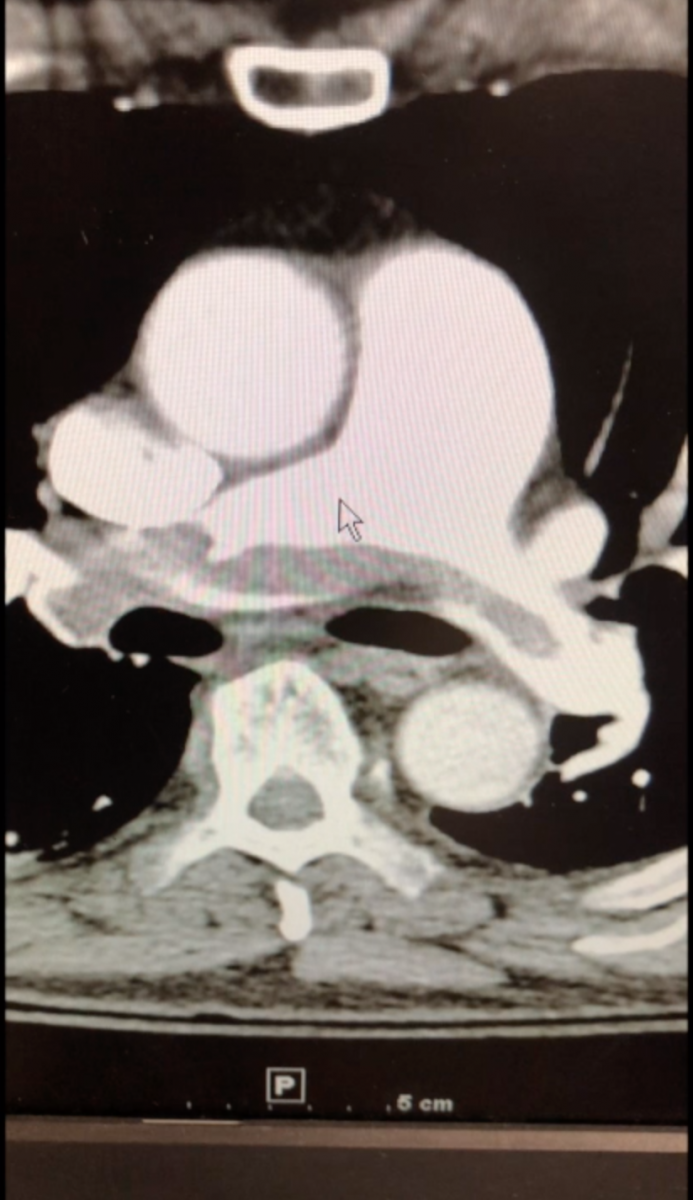

Surgical pulmonary embolectomy (SPE) is a safe and effective therapeutic approach to pulmonary embolism management for patients who are diagnosed with submassive and/or massive acute pulmonary emboli by clinical exam, supported by computed tomography (CT) and echocardiographic assessment. Other indications for surgical embolectomy include presence of thrombus-in-transit, concomitant cardiac pathology such as a large patent foramen ovale, or relative contraindications to thrombolytic therapy, including recent cerebrovascular or intracranial pathology, recent surgery, active bleeding, or other absolute contraindications to anticoagulation.

Encouraged by early results, the authors currently suggest that a minimally invasive approach for patients presenting with centrally located PE (main PA trunk or proximal right and left pulmonary artery branches) be considered specifically in patients with significant comorbidities or frailty. At this early stage of experience, and until the technique is further refined with the aid of specialized equipment, the authors recommend limiting this approach to proximal pulmonary artery embolic lesions.